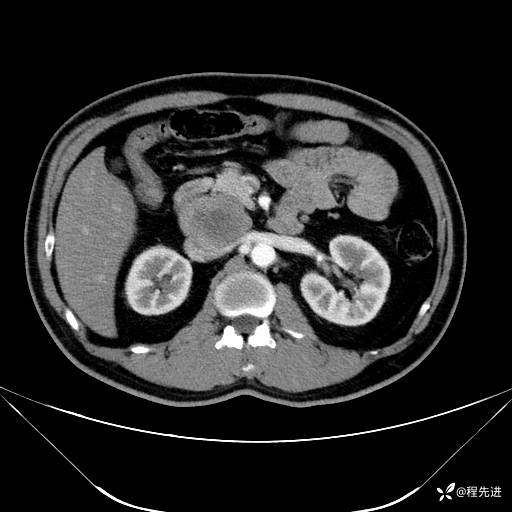

【腹盆】特别精彩病例|发现腹膜后肿物1月余

患者年龄:42岁

主诉:发现腹膜后肿物1月余

现病史:患者1月余前查体,行超声检查提示:后腹膜囊实性肿块;慢性胆囊炎伴胆囊内结石;无腹痛腹胀,不伴腹泻发热等;偶感腰背部酸痛。

CT平扫+增强: